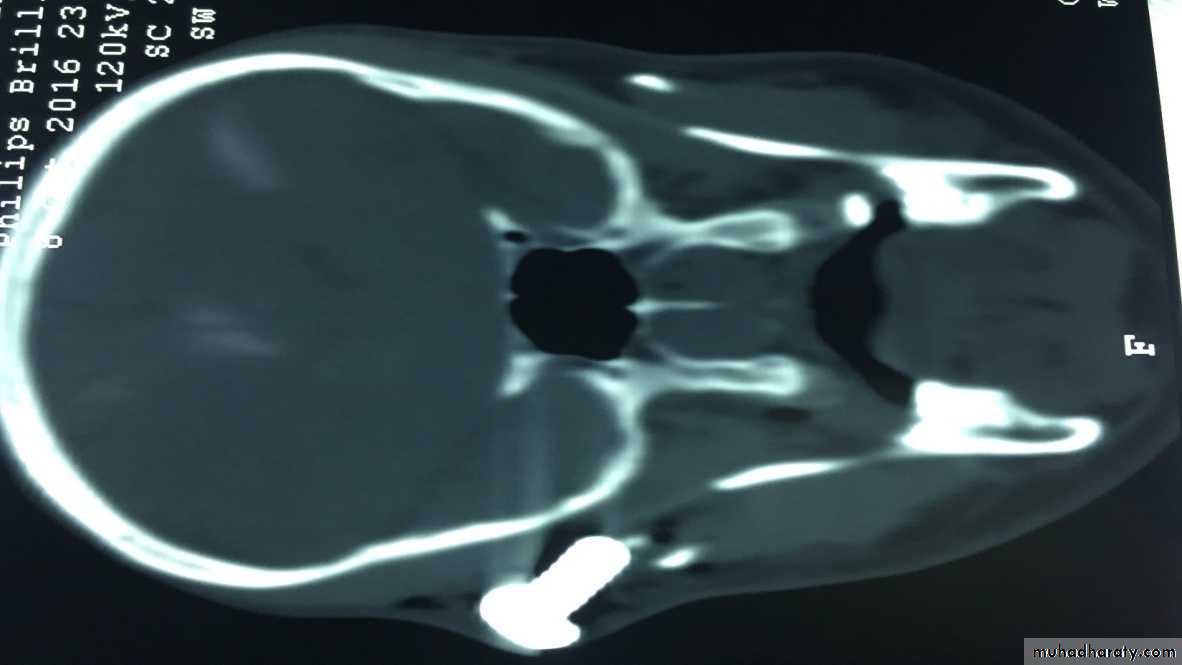

Clinical significance:

• Trigeminal neuralgia.• Blood supply of the face (for plastic surgery)

• Facial paralysis.

• Cavernous sinus thrombosis